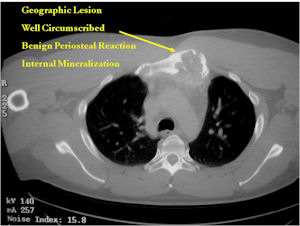

CT Scan:

- More useful for detecting mineralization and evaluating extent of bone destruction than plain X-ray

MRI:

- Also useful in determining extent

- There is often extensive edema around the tumor in the surrounding bone and soft tissues that can lead to a misdiagnosis of a malignant tumor.

- The periosteum remains intact around the soft tissue component. Might need a CT scan to detect the subtle calcification (Egg Shell Rim of Calcification) associated with an intact periosteal reaction

- The lesion may be entirely radiolucent but usually shows some degree of mineralization. Mineralization may appear stippled like cartilage but do not see chondroid pathologically. Mineralization is sometimes better detected on a CT scan rather than an x-ray.